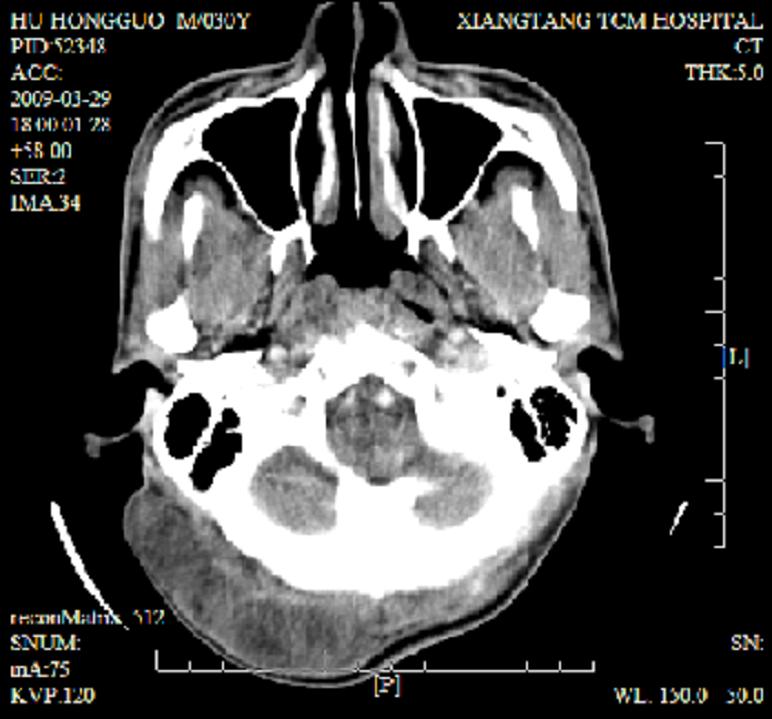

标题: CT19102:颈部肿块

男30y发现肿块3年

多处囊实性肿块,形态欠规则有一定形态,内见点状钙化,以囊变为主,增强后轻度强化,首先考虑神经源性肿瘤如鞘瘤,不除外脉管源性肿瘤如淋巴管瘤(见缝钻及囊性区域太多,如果合并感染完全可以这个影像表现),和海绵状血管瘤,但是血管瘤不太支持因为强化特征和病灶形态不典型.

右侧椎前间隙后部肌间、皮下囊性为主病变,可见分隔和点状钙化,分隔和壁呈轻度环形强化,大部分无强化。形态不规则,有钻缝特点。考虑1 淋巴管瘤合并感染2 血管平滑肌脂肪瘤3 表皮样囊肿4 不除外海绵状血管瘤。

病灶沿皮下及肌间隙爬行,病灶内有钙化灶,病灶有强化。病史3年,病人应该没什么症状。考虑纤维血管瘤可能性大。